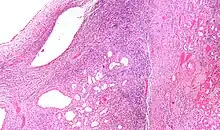

High magnification micrograph of a cystic nephroma showing the characteristic simple epithelium with hobnail morphology, and the ovarian-like stroma. H&E stain.

The characteristics of cystic nephromas are:

• Cysts lined by a simple epithelium with a hobnail morphology, i.e. the nuclei of the cyst lining epithelium bulges into the lumen of the cysts,

• Ovarian-like stroma that has a:

• Spindle cell morphology, and has a

• Basophilic cytoplasm.